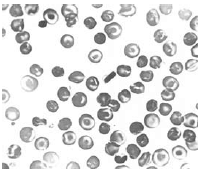

A figura mostra um esfregaço sanguíneo, cuja morfologia dos eritrócitos é encontrada nos pacientes com Hemoglobinopatia C homozigótica.